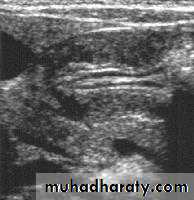

Hypertrophic pyloric stenosis refers to idiopathic thickening of gastric pyloric musculature which then results in progressive gastric outlet obstruction

In a normal situation, the pyloric muscle thickness (diame­ter of a single muscular wall on a transverse image) should normally be less than 3 mm (most accurate 3) and the length (longitudinal measurement) should not exceed 15 mm.